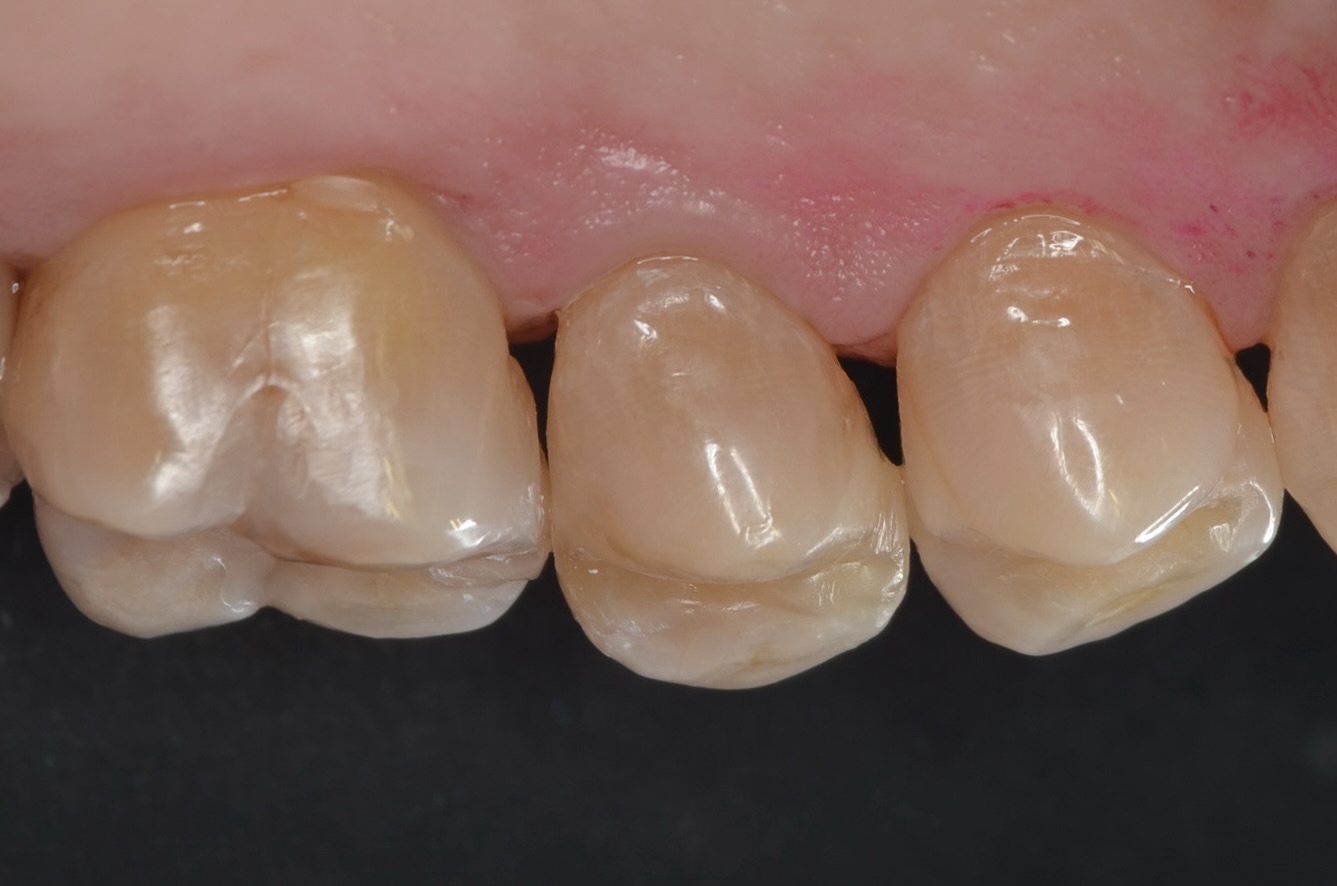

側方面観

歯頸部の虫歯も打イレクトボンディングで治療しました。 -

口蓋側面観

滑らかな曲線でフロスも引っかからないです。